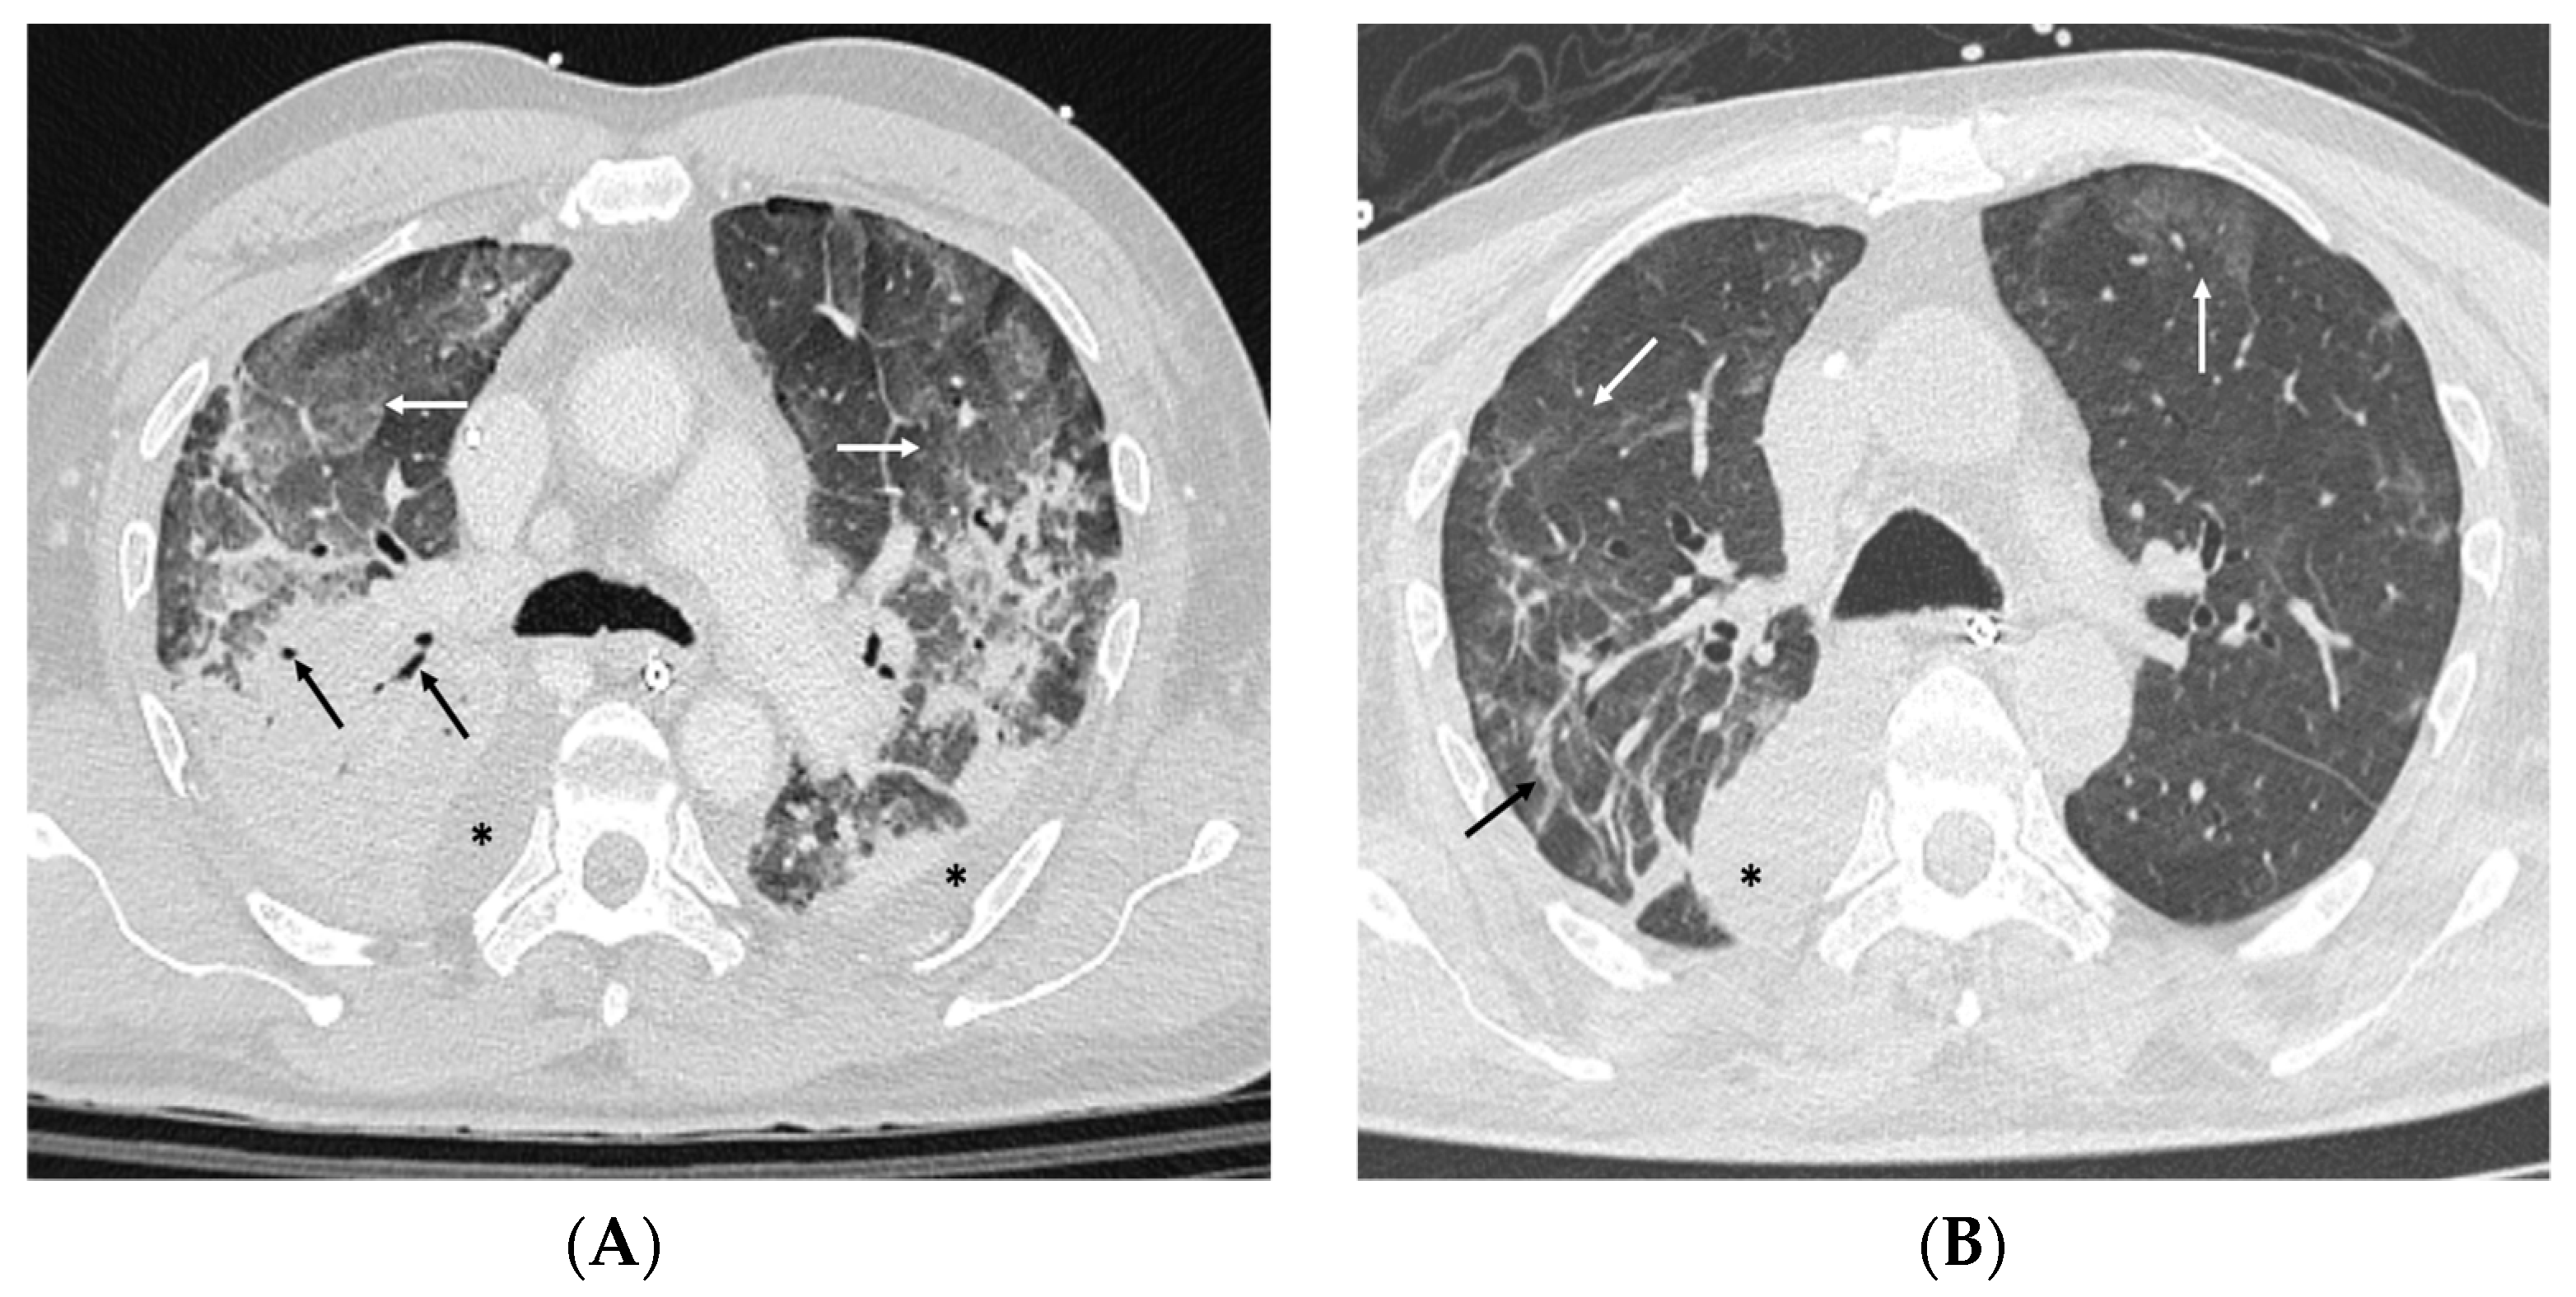

| 12 | Critical condition. Intubated and ventilated in SIMV (Vt 500 RR 16 PEEP 10 FiO2 80%) ECMO VV started (2320 rpm, BF 3, FGF 4, FiDO2 100%). | Chest/abdomen CT scan performed. | pH 7.43 pCO2 53 pO2 79 LAC 2.4 P/F 99 pH 7.50 pCO2 42 pO2 88 lactate 2.9 pH 7.40, pCO2 53, pO2 158, lactates 2.2 | Hemodynamics supported by noradrenaline in IC at 10 mL/h (4 mg:50 mL SF). Bactrim added to therapy. | |

| 26 | After curarization, under fibrobronchoscopic view, percutaneous tracheostomy is performed using the Griggs technique, placing a size 8 cannula, FBS is performed: thick secretions are aspirated (right > left). | Chest CT performed. | pH 7.56; pCO2 48, pO2 105, lactate 1.3; Hb 9.7, P/F 210, WBC 20,620 cells/mmc | Sedation suspended. | |